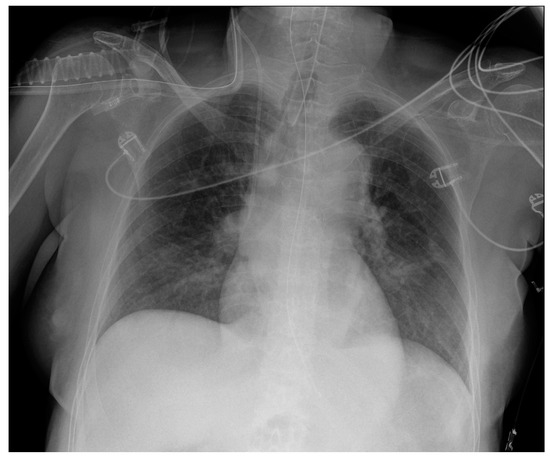

5. Cardiac Devices

5.2. Pacemaker (PM) and Automatic Implantable Cardioverter-Defibrillator (AICD)

5.3. Ventricular Assistance Devices (VADs)